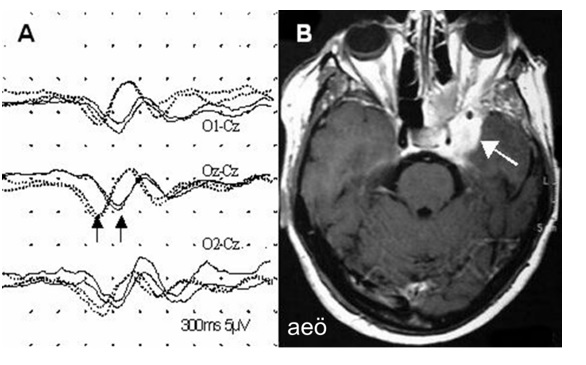

Şekil 3. Sol optik nörit nedeniyle incelenmekte olan 32 yaşındaki kadın

hastada patern VEP incelemesi. Sağlam (sağ) göz

uyarımı ile elde edilen yanıtlar kesik çizgiyle, sol göz uyarımı ile

kaydedilenler düz çizgi ile verilmiştir. Kortikal yanıtlar, solda belirgin

derecede uzun latanslı (oklar) ve düşük amplitüdlüdür.

Şekil 4. Altı yıl önce sol sfenoid kanat meningiomu

nedeniyle ameliyat edilen (parsiyel rezeksiyon) 64

yaşında kadın hasta. Sol gözünde vizyon azalmasının

belirginleşmesi ve solda papilödem nedeniyle

incelenmiştir. Şekil B’de kontrastlı T1 transversal MR kesitinde tümör kalıntısı (ok), Şekil A’da

ise oksipital orta hat (Oz), sol (O1) ve sağ (O2) paramedian yerleşimli elektrodlardan

verteks (Cz) referansı ile

kaydedilen patern VEP yanıtları görülmektedir. Sağlam

(sağ) göz uyarımı ile kaydedilen yanıtlar kesikli, sol göz uyarımı ile

kaydedilenler düz çizgi ile verilmiştir. Sol taraf uyarımı ile elde edilen

yanıtların latansları belirgin uzundur.